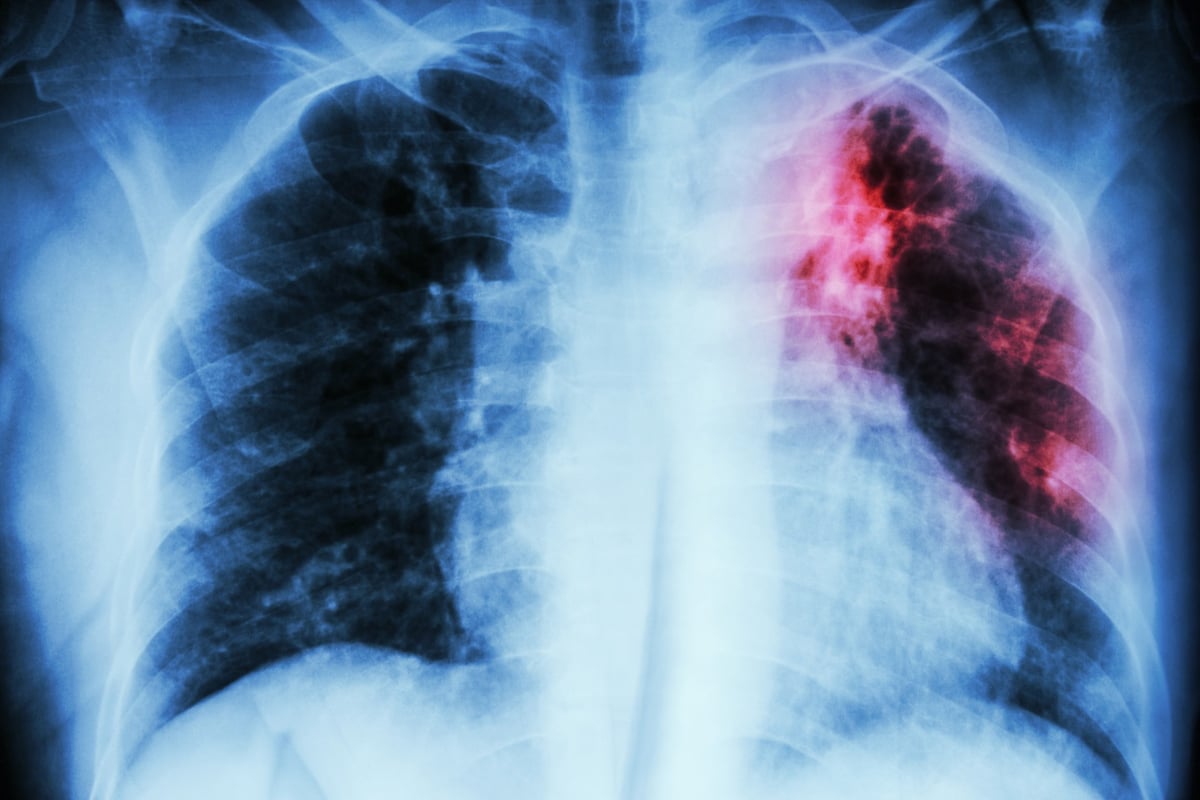

John Green on how tuberculosis, the world’s deadliest disease, is completely curable and the roadblock to helping rid the world of it is money. “The tests are great. If only we could afford them.”